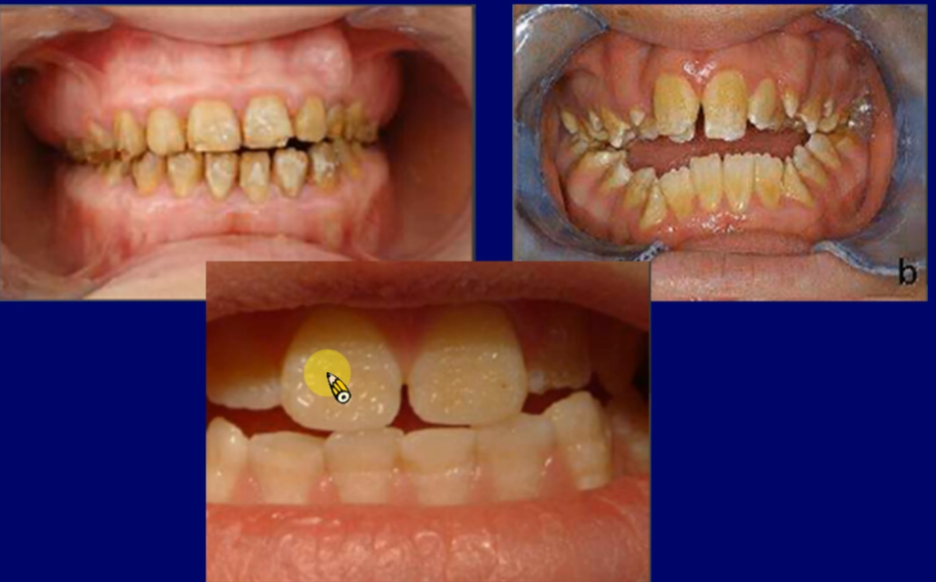

Amelogenesis imperfecta

amelogenins

Ameloblastin

Enamelin

Enzymes (打斷 protein)